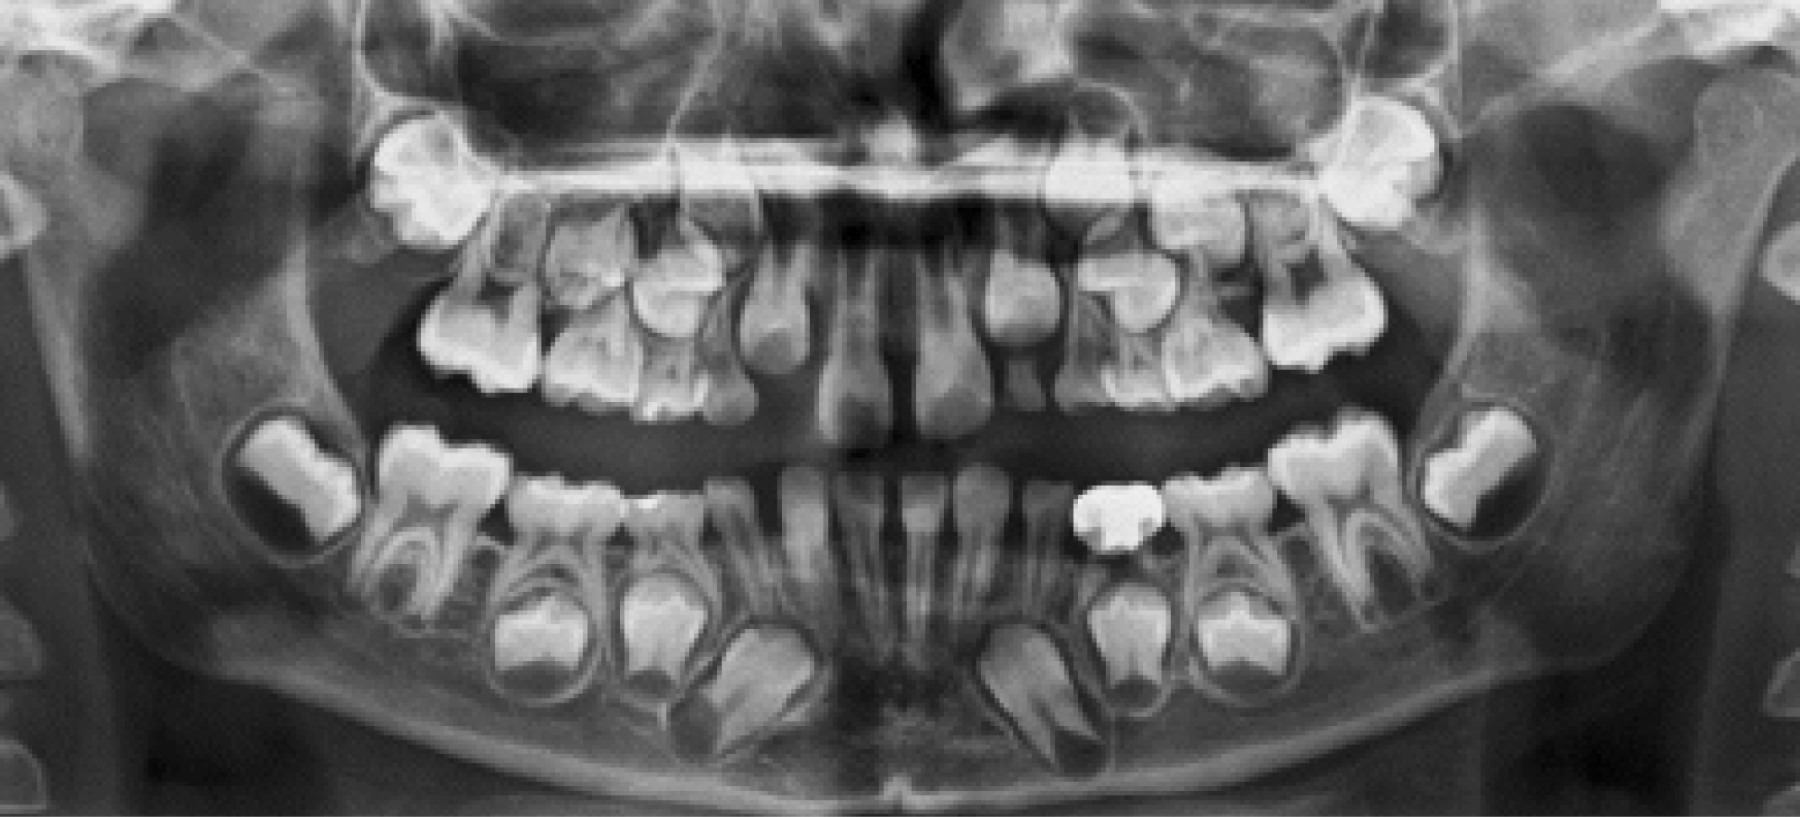

El examen intraoral reveló dentición mixta y ausencia del órgano dentario (OD) 4.3, con abombamiento de la cortical vestibular que se extiende desde el OD 4.2 al OD 3.2. Se solicita tomografía computarizada Cone-Beam (TCCB) y radiografía panorámica, donde se observa el OD 4.3 retenido en la zona anteroinferior de la mandíbula, con una franca mesioversión, con saco pericoronario levemente ensanchando, y asociado a disrupción de la cortical vestibular (Figura 2).

Figura 2